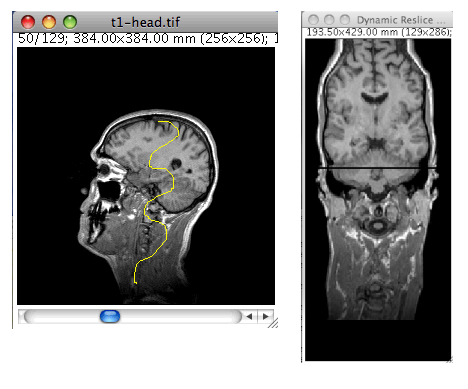

Dynamic Reslice

Description

Reslice